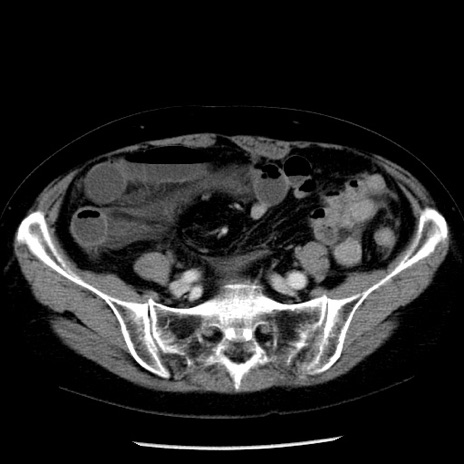

冠状断像

【症例】70歳代女性

【主訴】腹痛、嘔吐

【現病歴】15時間程前(昨晩)より腹痛あり。今朝になっても症状の改善なく、嘔吐あり。腹痛も増悪あり、救急外来受診。

【既往歴】子宮癌全摘術後

【身体所見】意識清明、BP 121/72mmHg、P 74bpm、SpO2 100%(RA)、腹部:平坦・軟、腸雑音ほぼ聴取せず。下腹部・心窩部・臍左上に圧痛あり。反跳痛なし。

【データ】WBC 10600、CRP 0.15